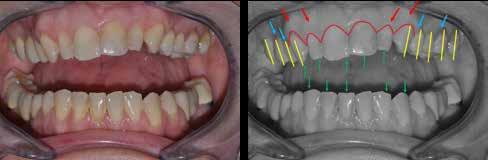

Dr. Csillag MáriaA komplex esztétikai munkák készítésekor óhatatlanul funkcionális megoldásra is váró esetekkel találkozunk, amelyek nagy többségében temporomandibuláris ízületi fájdalmakkal járnak, és diszfunkciókkal járó kórképeket is kezelnünk kell. A fogak érintkezésének kialakításakor így nem elegendő az esztétikai irányelveket alkalmaznunk, hanem egy komplex szemléletrendszerre, ezen belül az okklúzióról tanult ismereteinkre is szükségünk van.

Minden rendszer, probléma akkor lesz átlátható és megfejthető, ha több szemszögből is vizsgáljuk (1. kép). A képen ugyanaz a formarendszer látható más-más perspektívából szemlélve: egy kör, melynek középpontján egy egyenes halad át. Az egyik oldalról keresztként látható, a másik oldalról egy kör, közepében pont figyelhető meg. A helyes fogérintkezések kialakításakor is célszerű több szempont szerint megvizsgálni a helyzetet, és igénybe venni a megoldásokhoz különböző diagnosztikai, illetve megvalósítási módszert is. Így segítségünkre lehet az egyedi középvonal-rendszerek is-

frontfogak esztétikailag is kellemetlen megjelenést biztosítanak, ugyanakkor mivel a frontfog stop nem elégséges, így az állkapocs előrecsúszását eredményezi, majd a fogak a nagymetszőkön támaszkodva további funkcionális problémát is okoznak. A fogérintkezés problémái az izomzatban is jelentkeznek, a kompenzációk szinte azonnal láthatók az arcon, később a test izmain, a testtartáson is. Különböző fogérintkezési problémák izomkompenzációs mintázata teljesen típusos megjelenésű, leolvasható a testtartásból, sőt az arcról is.

merete, az arcredő diagnosztika, az izomdiagnosztika (Smylist besorolás), a TMI-ről alkotott tudásunk, a CT/MRI vizsgálatok, az egyedi artikulátorok és a miotómok alkalmazása, esetlegesen arcívek használata, továbbá a digitális tervezés is (2. kép). A Smylist Módszer például összetett szemlélettel közelíti meg az okklúzió kérdését. A maxilla fogainak állását, elhelyezkedését az arckoponyából számolva tervezi meg, a mandibula fogainak érintkezését pedig az izomdeprogramálással meghatározva hozzárendeli a már kialakított maxilláris fogakhoz. Az okklúziót egyetlen helyes pozícióban tudja elképzelni, ahol minden izom feszülésmentes. Minden egyes paraméternek, dőlésnek jelentősége van mind az esztétikai, mind pedig a funkcionális téren. A láthatóan nem esztétikus megjelenés biztosan rejt magában funkcionális problémát is. Például egy kijjebb álló szemfog esztétikailag sem ad megfelelő látványt, de laterális stop és szemfogvezetés hiánya miatt funkcionális gondot is fog okozni. A rövidre tervezett

Sajnos a megoldásra váró komplex eseteink többségében azonban aszimmetrikus izomműködéssel állunk szemben, amelyben egy dinamikusan változó fogérintkezést figyelhetünk meg egy-egy időpillanatban. Így az adott okklúzió a legtöbb esetben illúzió, hiszen folyamatosan változik, azonban a fogmigrációs folyamat lassú dinamikája miatt ez a változás csak évek alatt érzékelhető (5. kép). Így szigorúan véve, minden fogazatot érintő beavatkozás – amennyiben nincsen megfelelő izomszimmetria – csupán egy instabil rendszerben való építkezési kísérlet, amelynek eredménye logikai alapon is a 24 gomphózis ízületi komplexum adott elemeinek – egy-

egy fog vagy gyökér körüli terület, vagyis ízület – biztos túlterhelése lesz. (Ennek mintázata egyébként az izomműködés aszimmetriájából, az állkapocs rotációjából adódóan teljesen típusos a Smylist besorolás szerint). A fogorvos feladata tehát minden egyes komplex és nem komplex beavatkozás esetén az lenne, hogy ezt az adott izomszimmetriát a megfelelő okklúzális viszonyok kialakításának biztosítása érdekében megteremtse, illetve megtartsa. A Smylist rendszerben az állkapocs nyugalmi helyzetében létrejövő fogérintkezést, okklúziót BOP-nek (Balanced Occlusal Position) nevezzük. Minden más izomspazmussal járó állkapocs helyzetben létrejövő fogérintkezést FOP (Forced Occlusal Position), azaz forszírozott, erőltetett állkapocs pozíciónak hívjuk. Ennek az izomaszimmetriának a jelei rögtön mutatkoznak nem csak a rágóizomzatban, hanem a mimikai izomzatban is, izomelváltozásokat okozva az arcon. Ezek az izomeltérések jellemzőek lehetnek egy-egy izomcsoportra, illetve az arc egészére is típusos képet adnak: masseterhipertófia, mentális izom megnagyobbodása, zygomatikusz izom aszimmetrikus ellapulása (6. a-b-c kép) Minden BOP-ben, azaz harmonikus, izomszimmetriában kialakított fogérintkezésben készülő komplex esztétikai beavatkozás, fogszabályozási terápia, implantprotetikai megoldás stabil, problémamentes eredményt ad, hiszen aszimmetrikus erők nem fognak fellépni a pótlások átadása után. Azonban, ha a munkák FOP-ben készülnek, akkor számítani kell a héjak, koronák lepattanására, az implantációs pótlások esetleges kimozdulására, a parodontális esztétikai műtétek siker-rátájának csökkenésére, a fogszabályzó kezelések eredményének kollapszusára. Ezekben a helyzetekben a fogakat jelentős aszimmetrikus izomerő éri. Ahhoz, hogy ez ne történjen meg, az izmokat deprogramálni kell, amelyre többféle módszer is létezik. Az izomdeprogrammálást követően egy olyan állkapocshelyzet jön létre, amely viszonyításként megmutatja, hogy a fogaknak hol kellene érintkezniük (6. kép). Ebben a relációban szükséges kialakítani a helyes fogérintkezéseket, a frontfogak, szemfogak közötti stopokat, a Spee- és a Wilson görbéket, a hármas egységeket, továbbá a fogak ötpontos érintkezéseit (7. a-b kép). Fontos ezen kívül a megfelelő overbite és overjet kialakítása, a fogexpozíció mértéke, és a fogak, ajkak viszonyának helyes kialakítása is.